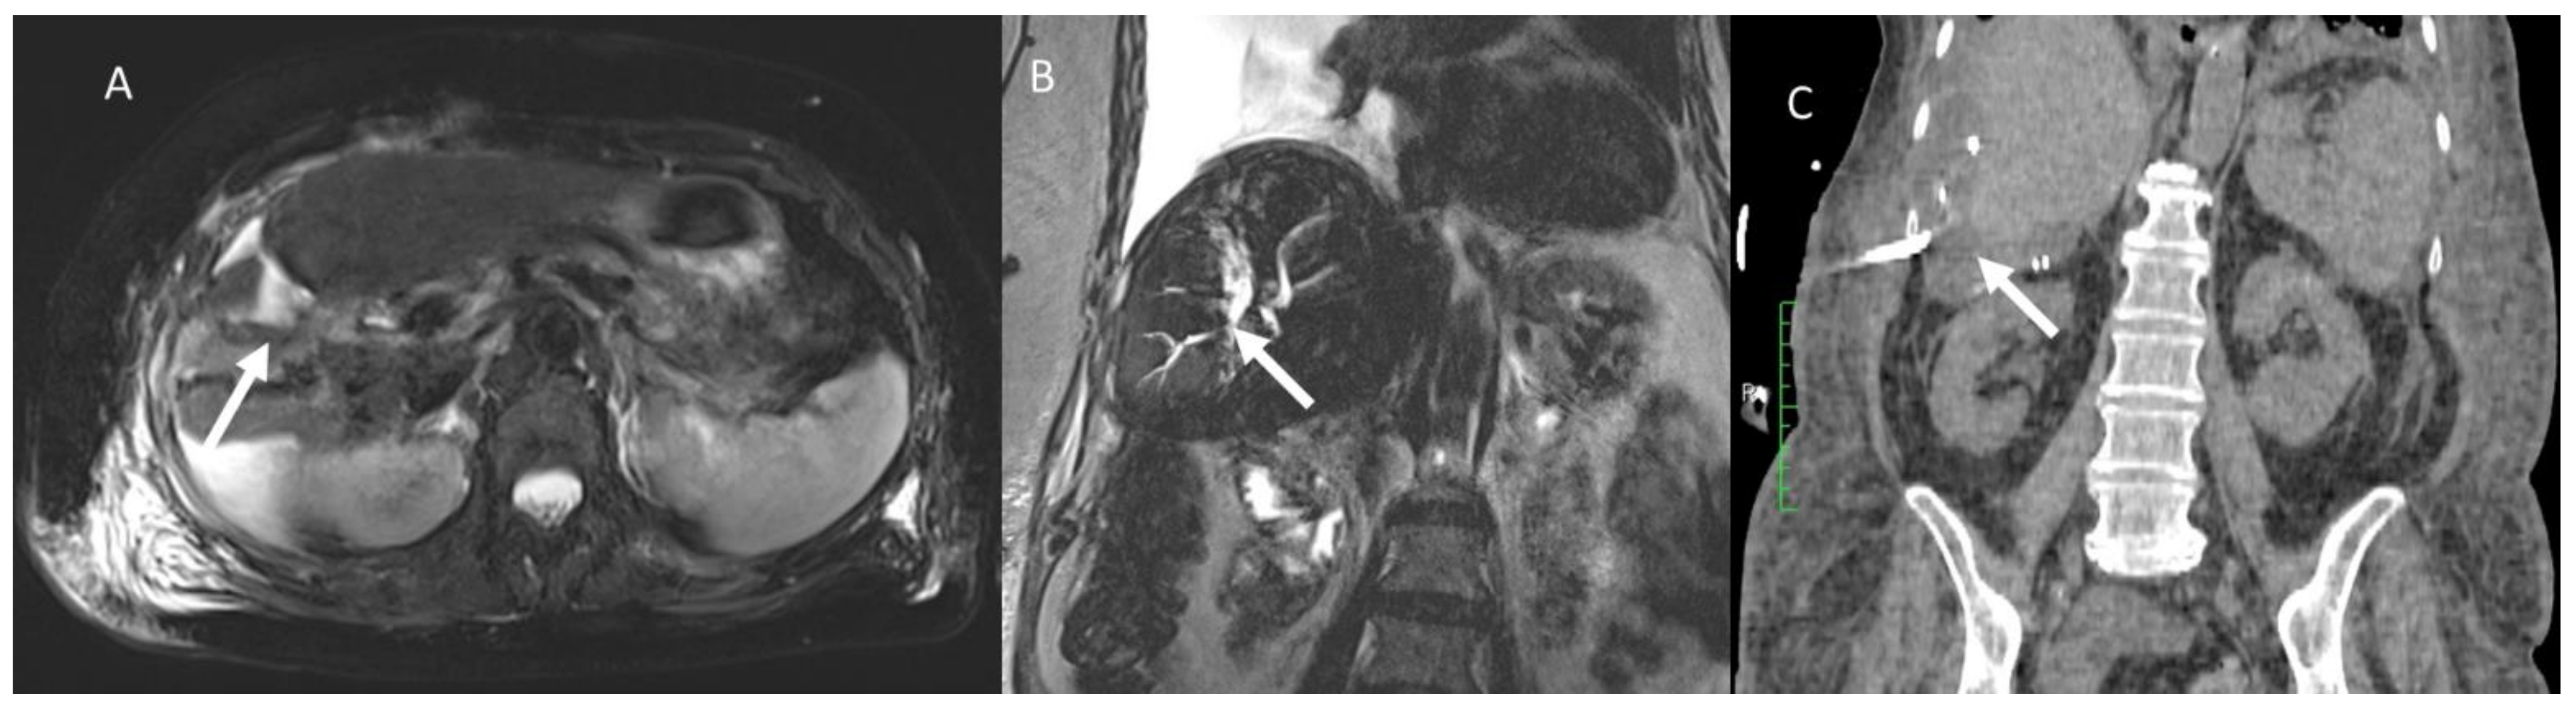

- Granata, V.; Fusco, R.; Catalano, O.; Piccirillo, M.; De Bellis, M.; Izzo, F.; Petrillo, A. Percutaneous Ablation Therapy of Hepatocellular Carcinoma with Irreversible Electroporation: MRI Findings. Am. J. Roentgenol. 2015, 204, 1000–1007. [Google Scholar] [CrossRef] [PubMed]

- Granata, V.; Castelguidone, E.D.L.D.; Fusco, R.; Catalano, O.; Piccirillo, M.; Palaia, R.; Izzo, F.; Gallipoli, A.D.; Petrillo, A. Irreversible electroporation of hepatocellular carcinoma: Preliminary report on the diagnostic accuracy of magnetic resonance, computer tomography, and contrast-enhanced ultrasound in evaluation of the ablated area. Radiol. Med. 2016, 121, 122–131. [Google Scholar] [CrossRef]